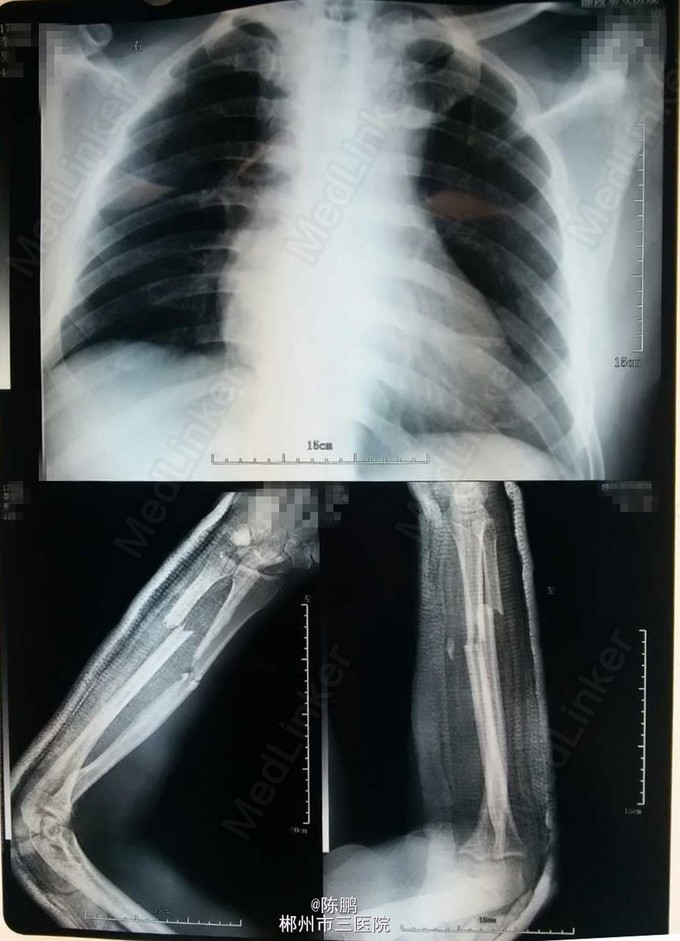

患者中年男性,43岁; 主诉:外伤后头部疼痛,流血,左前臂及左小腿肿痛,不能活动18小时。 现病史:患者18小时前被人打伤后,致头部疼痛,流血,左前臂及左小腿肿胀不能活动,当时昏迷不省人事,具体时间不详,在外院行清创缝合,夹板固定后,于今日来我院就诊。

专科体查:左前臂明显肿胀,局部皮肤青紫,压痛,纵向叩击痛,可扪及明显骨擦感及闻及骨擦音,左前臂活动受限,左桡动脉搏动可,左小腿少肿胀,局部皮肤青紫,压痛,纵向叩击痛,中下1/3处可扪及明显骨擦感及闻及骨擦音,左小腿活动不能,左足背动脉搏动可,肢端血运感觉可,余肢体及脊柱未见异常。 辅查:x线示:左尺桡骨,左胫骨下段,左腓骨上段骨折

诊断:1.左尺桡骨骨折 2.左胫骨下段腓骨上段骨折 3.头部外伤:1)脑震荡 2)头皮挫裂伤 3)颅内血肿脑挫裂伤待查 行左胫骨下段骨折切开复位带锁钉内固定及左尺桡骨下段骨折切开复位,钢板内固定术